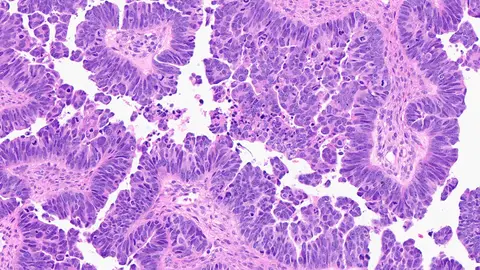

Como en la mayoría de los tumores, las características celulares son determinantes. Puede que la base esté en los carcinomas epiteliales (que son la mayoría) no será tan agresivo como si se produce en los tumores germinales (mucho más infrecuentes).

Ahora, un nuevo estudio, publicado en Proceedings of the National Academy of Sciences, explica las bases genéticas de una forma rara y agresiva de cáncer de ovario y ofrece una posible vía para nuevos tratamientos. Se trata del carcinoma seroso de alto grado, uno que suele comenzar en la trompa de Falopio antes de propagarse a los ovarios y otros órganos pélvicos. Este cáncer suele detectarse en una etapa avanzada y se vuelve resistente a las quimioterapias actuales. Su genética subyacente es compleja, con múltiples alteraciones e inestabilidades genéticas. Uno de los genes implicados es el CDK12.

"Estas características, que comparten el modelo y los humanos, incluyen no solo la célula de origen y su apariencia al microscopio, sino también el momento del desarrollo tumoral, la genética subyacente, las alteraciones genéticas adquiridas y los perfiles de expresión génica, el microambiente tumoral (incluidos los componentes de las células inmunitarias) y otros aspectos del comportamiento biológico", añade Cho.